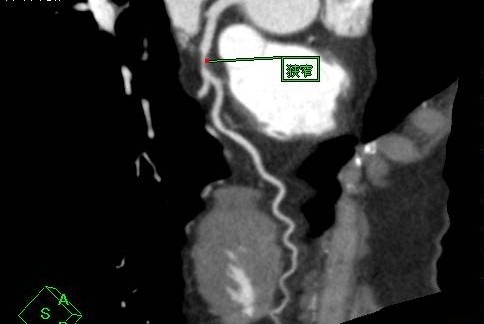

冠動脈CT(冠A-CT)検査について

当院では、冠動脈CT(冠A-CT)検査を行っております。

冠A-CT検査は、心臓の血管(冠動脈)をCTで詳しく調べる検査で、カテーテル検査の前段階として行える、体への負担が比較的少ない検査です。

冠動脈の狭窄(血管の狭くなり)や動脈硬化の状態を画像で確認することができ、自覚症状が出る前の早期の狭心症の発見や、将来の心筋梗塞のリスク評価(予知)に役立ちます。

画像検査

X線CT装置で心臓を画像化するという試みは以前からありましたが、検査のためには息止め時間が最短でも40秒と非常に長く、患者さんに大きな負担を与えてきました。導入されているCT装置は、世界で初めて心臓の検査(120mmのスキャン範囲)を8秒の息止め時間で可能にした装置ですので患者さんの負担を大幅に軽減することが可能です。また立体像(3次元画像)として撮影部を360度自由な方向から観察することが可能です。

このX線CTを使用することにより、従来の画像診断装置では困難であった無症状の心血管の狭窄(きょうさく:せまくなっている)を早期に発見したり、カテーテル治療(細い管を体内に挿入し、その先端を風船状に膨らませて心血管の狭窄部分を広げたりする治療)のフォローアップ検査装置として期待されています。